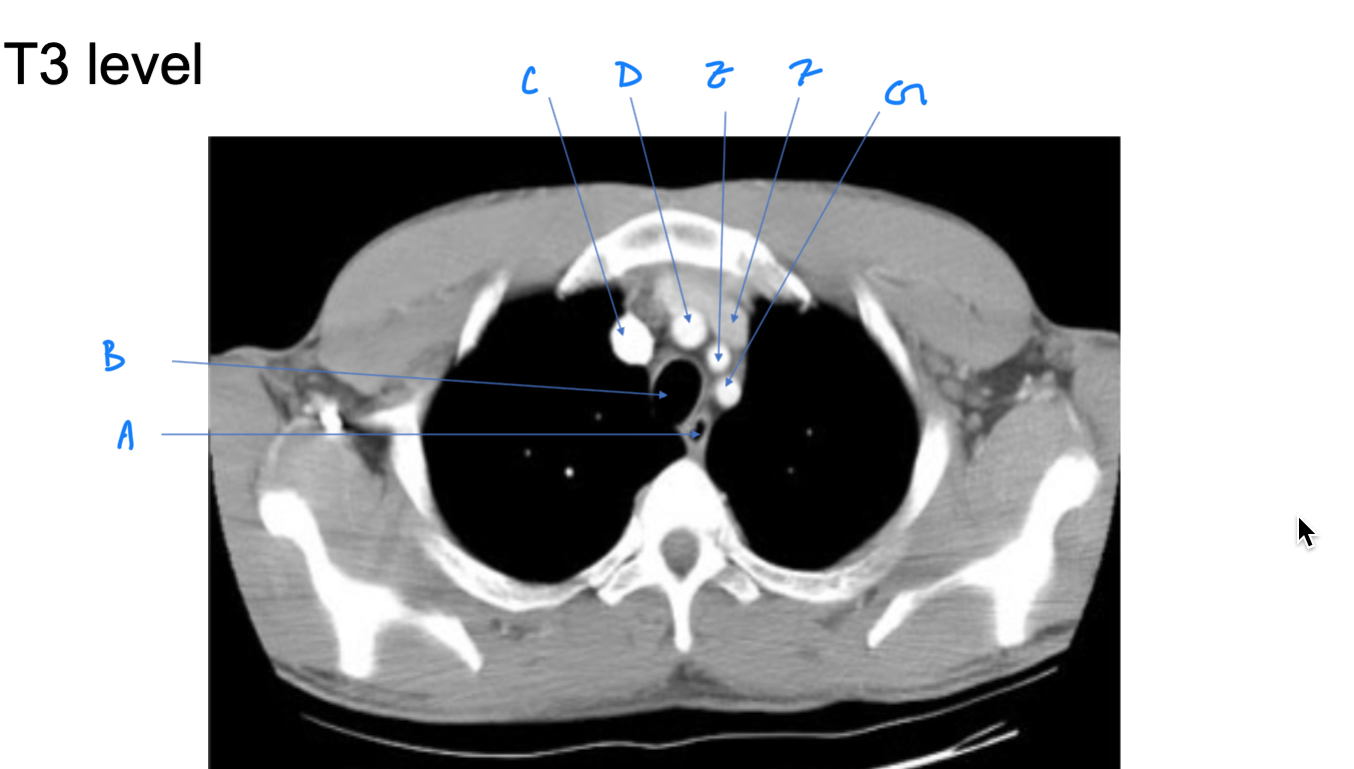

Esophagus

A. Identify

Trachea

B. Identify

R Brachiocephalic v.

C. Identify

Brachiocephalic trunk

D. Identify

L CCA

E. Identify

L Brachiocephalic v.

F. Identify

L Subclavian a.

G. Identify